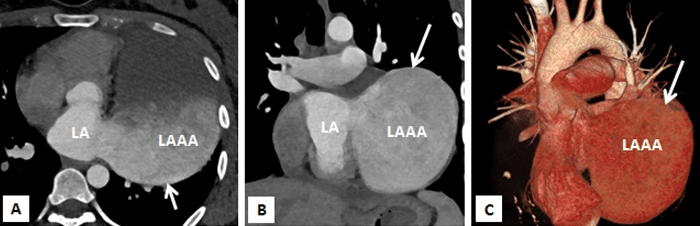

Figure 3A-3C: Computed tomography with multiplanar reconstructions (A and B) and volume rendered image (C) demonstrating a giant left atrial appendage aneurysm with a wide neck. It confirmed that the left sided cardiac prominence corresponds to the left atrial appendage (LAAA).

Multi-slice row computed tomography and magnetic resonance imaging was done that showed a large contrast-enhancing chamber continuous with the left atrium via a wide neck. The left atrium was grossly normal in size itself and a wide neck of 4.0 cm lead to a large aneurysm measuring 8.33 x 7.01 x 4.0 cm. The left anterior interventricular coronary artery was closely seen in relation to the communicating neck and was normal as were the other coronaries. Lower down, the aneurysm was lying adjacent to the lateral wall of the left ventricle which showed normal wall thickness and cavity size. The pulmonary veins were located at their normal anatomical positions with no evidence of stenosis (Figures 3A-3C, 4A, 4B). Considering the size of the left atrial appendage aneurysm with supraventricular arrhythmias and deteriorating clinical symptoms, the patient was medically stabilised and was considered for aneurysectomy of the left atrial appendage. The operation was performed under normothermic cardiopulmonary bypass using angled venous cannulae (Edwards Life Sciences Research Medical Inc, West Midvale, Utah) into the superior and inferior caval veins and aortic cannulation. St.Thomas-II cold blood cardioplegic solution (1:4) and topical hypothermia was used for myocardial preservation. The right pleural cavity was opened, and the heart was dislocated within the right pleural cavity.